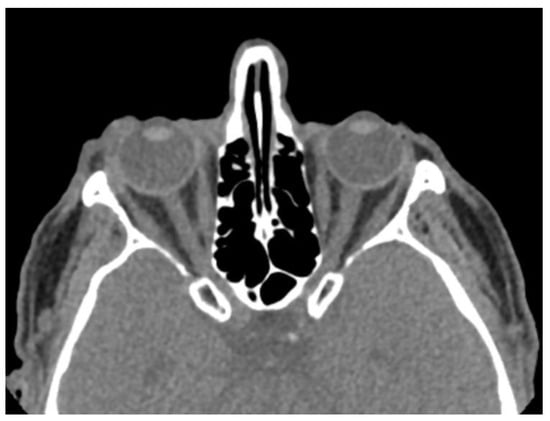

| Globe wall irregularity | 16 (53.3) |

| Asymmetric anterior chamber depth | 16 (53.3) |

| Decreased globe volume | 6 (20.0) |